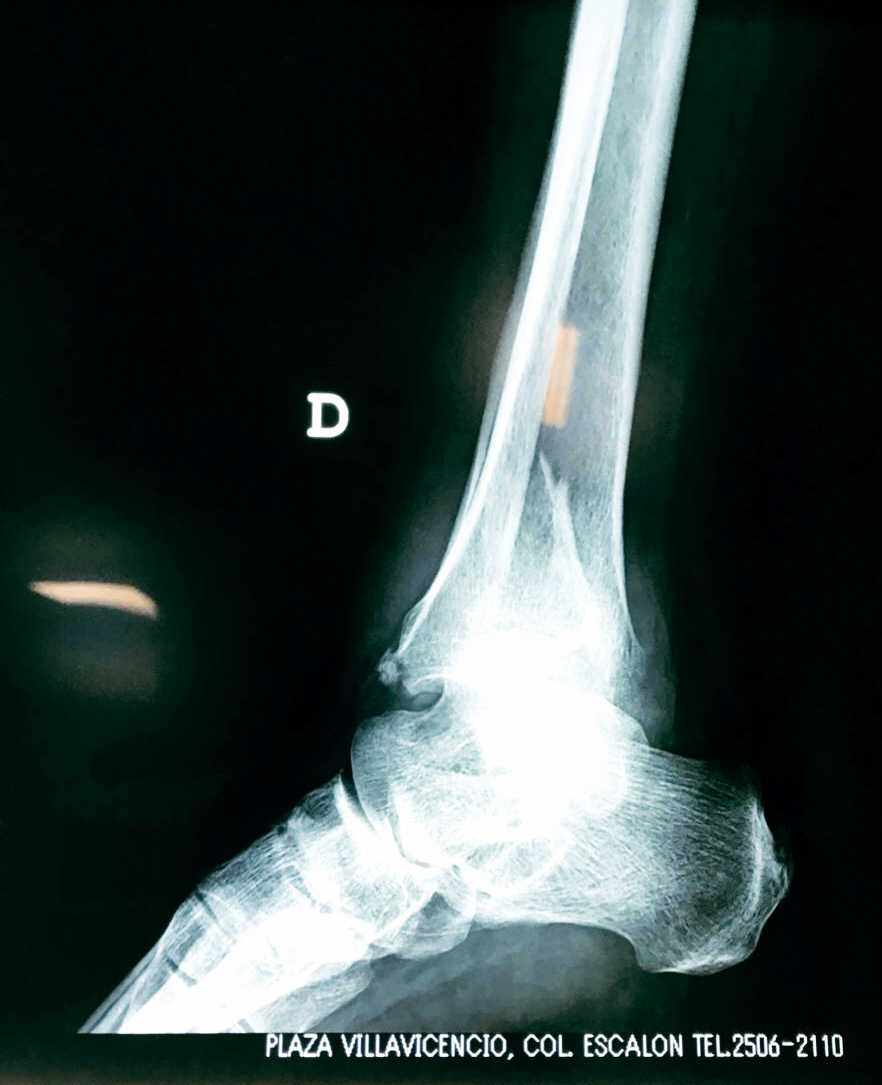

Algunas fracturas de tobillo pueden requerir cirugía si:

- Los extremos de los huesos están desalineados entre sí (desplazados).

- La fractura se extiende hasta la articulación del tobillo (fractura intra-articular).

- Los tendones o ligamentos (tejidos que sujetan los músculos y los huesos entre sí) están rotos.